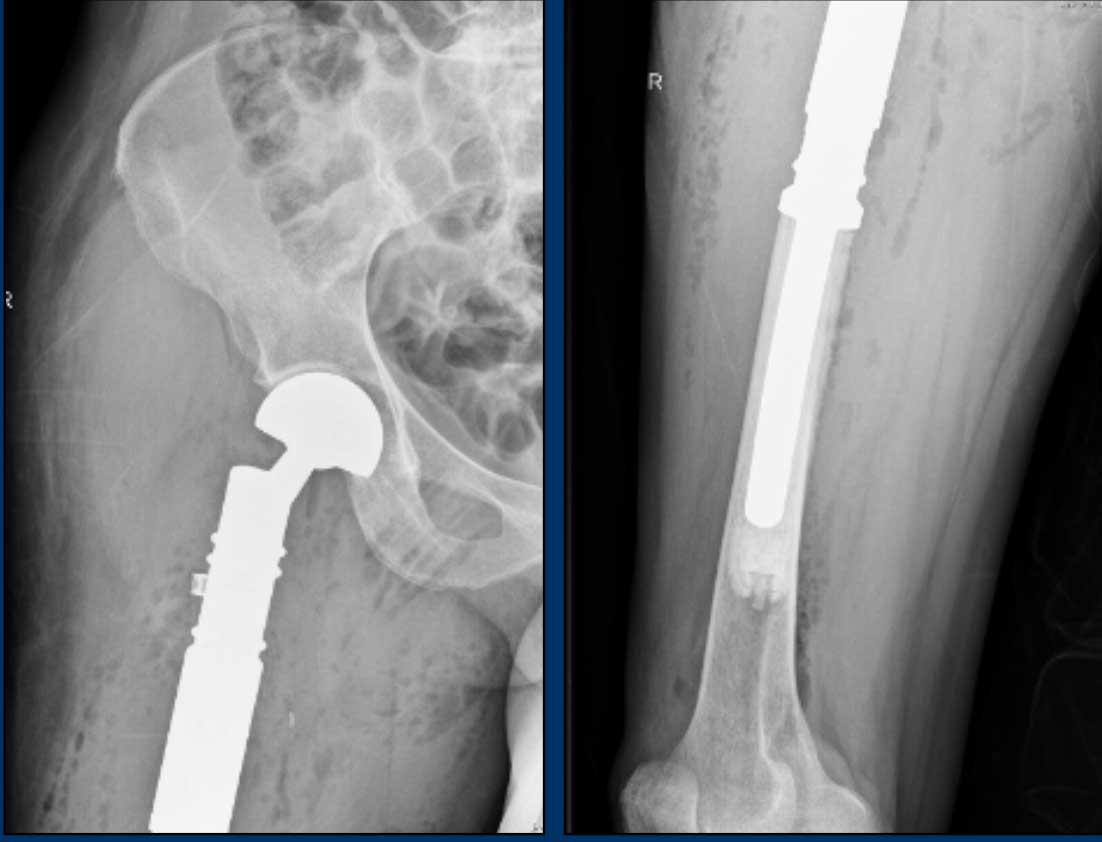

Hình ảnh

Có một tổn thương tiêu xương, dạng giãn rộng ở thân xương đùi phải đoạn gần.

Có hiện tượng dày vỏ xương nhẹ lân cận mà không có phản ứng màng xương.

Không thấy chất nền sụn rõ ràng trên phim X-quang này.

Kết luận

Chẩn đoán phân biệt bao gồm sarcoma sụn, loạn sản xơ, u lympho, di căn và u tương bào.

Chụp CT không tiêm thuốc cản quang có thể giúp phát hiện các vôi hóa chất nền sụn nhỏ trong trường hợp này. Tuy nhiên, chúng tôi đã tiến hành thẳng vào MRI.

Hình ảnh T1W cho thấy sự thay thế tủy xương.

Hình ảnh T2W cho thấy phản ứng màng xương

và phù tủy xương quanh tổn thương.

Bản thân khối u tăng tín hiệu và

có dạng nốt.

Hình ảnh T1W FS sau tiêm Gd cho thấy

hình thái ngấm thuốc dạng vòng và cung.

Tất cả những phát hiện này phù hợp với một khối u sụn, và rất nghi ngờ là u sụn ác tính độ II hoặc cao hơn.

Tại trung tâm chuyên khoa tuyến ba về sarcoma xương của chúng tôi, chúng tôi không thực hiện sinh thiết đối với các khối u sụn này, vì điều này có thể gây ra sai số lấy mẫu do tính không đồng nhất bên trong khối u.

Bạn có thể vô tình sinh thiết vào phần lành tính hơn của khối u và đánh giá thấp độ mô học.

Các khối u sụn được biết đến với khả năng gieo rắc theo đường sinh thiết.

Continue with the postoperative

X-rays…..

Điều trị bao gồm cắt bỏ khối xương đùi gần và tái tạo bằng nội khớp giả.

Pathology confirmed a chondrosarcoma grade II.

Chondrosarcoma độ II và độ III không thể phân biệt dựa trên hình ảnh học.

Đây là chẩn đoán được thực hiện dựa trên mô bệnh học.

Do đó, chúng tôi gọi các tổn thương như vậy là “độ II hoặc cao hơn” trong báo cáo chẩn đoán hình ảnh của chúng tôi.